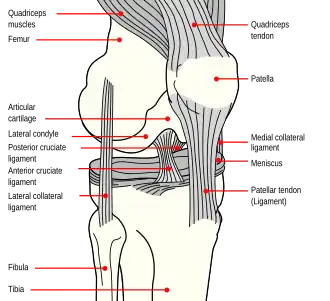

Pathophysiology

The knee joint is formed by three bones: the femur (thighbone), the tibia (shinbone), and the patella (kneecap). These bones are held together by ligaments, which are strong bands of tissue that keep the joint stable while an individual is walking, running, jumping, etc. There are two types of ligaments in the knee: the collateral ligaments and the cruciate ligaments.

The collateral ligaments include the medial collateral ligament (along the inside of the knee) and the lateral or fibular collateral ligament (along the outside of the knee). These two ligaments function to limit sideways movement of the knee.[6]

The cruciate ligaments form an “X” inside the knee joint with the anterior cruciate ligament running from the front of the tibia to the back of the femur, and the posterior cruciate ligament running from the back of the tibia to the front of the femur. The anterior cruciate ligament prevents the tibia from sliding out in front of the femur and provides rotational stability.[6]

There are also two C-shaped structures made of cartilage called the medial meniscus and lateral meniscus that sit on top of the tibia in the knee joint and serve as cushion for the bones.[1]

|

| Right knee, front, showing interior ligaments | Left knee, behind, showing interior ligaments |